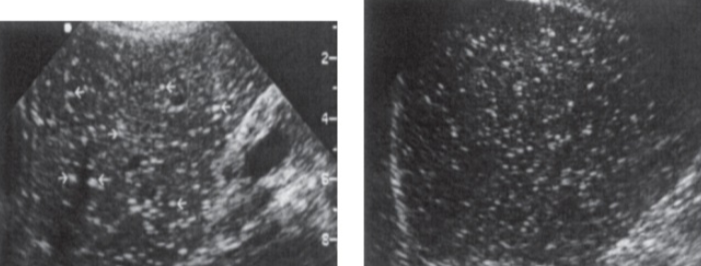

echinococcal cyst

echinococcal cyst (squiggle lines is the water lily sign)